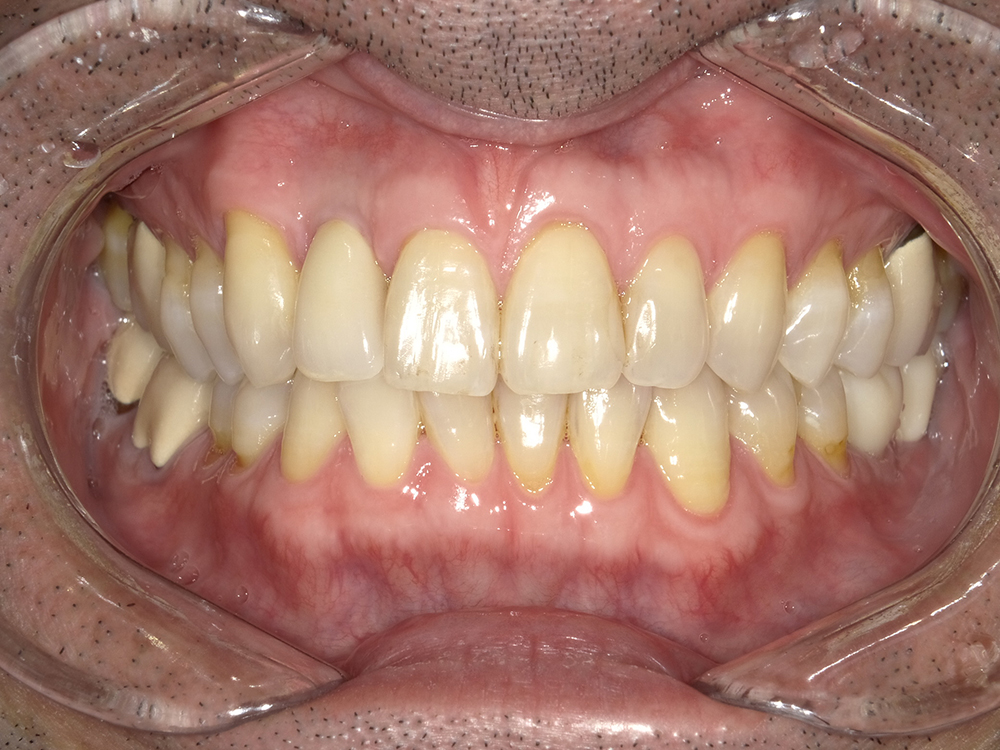

55歳 男性

- 主訴

- 前歯でしか咬めなく、食事を採るのに非常に困難で辛い

- 処置内容

- 上顎6本、下顎3本

- 治療費用

- 上顎:約230万(税込)下顎:約120万(税込)

- 治療期間

- 上顎:1年(仮歯まで8か月)下顎:8か月(仮歯まで5か月)

- リスク

- 上部構造物、仮歯の破折、術後の腫れ(3日)、人工歯根脱落リスクがあります